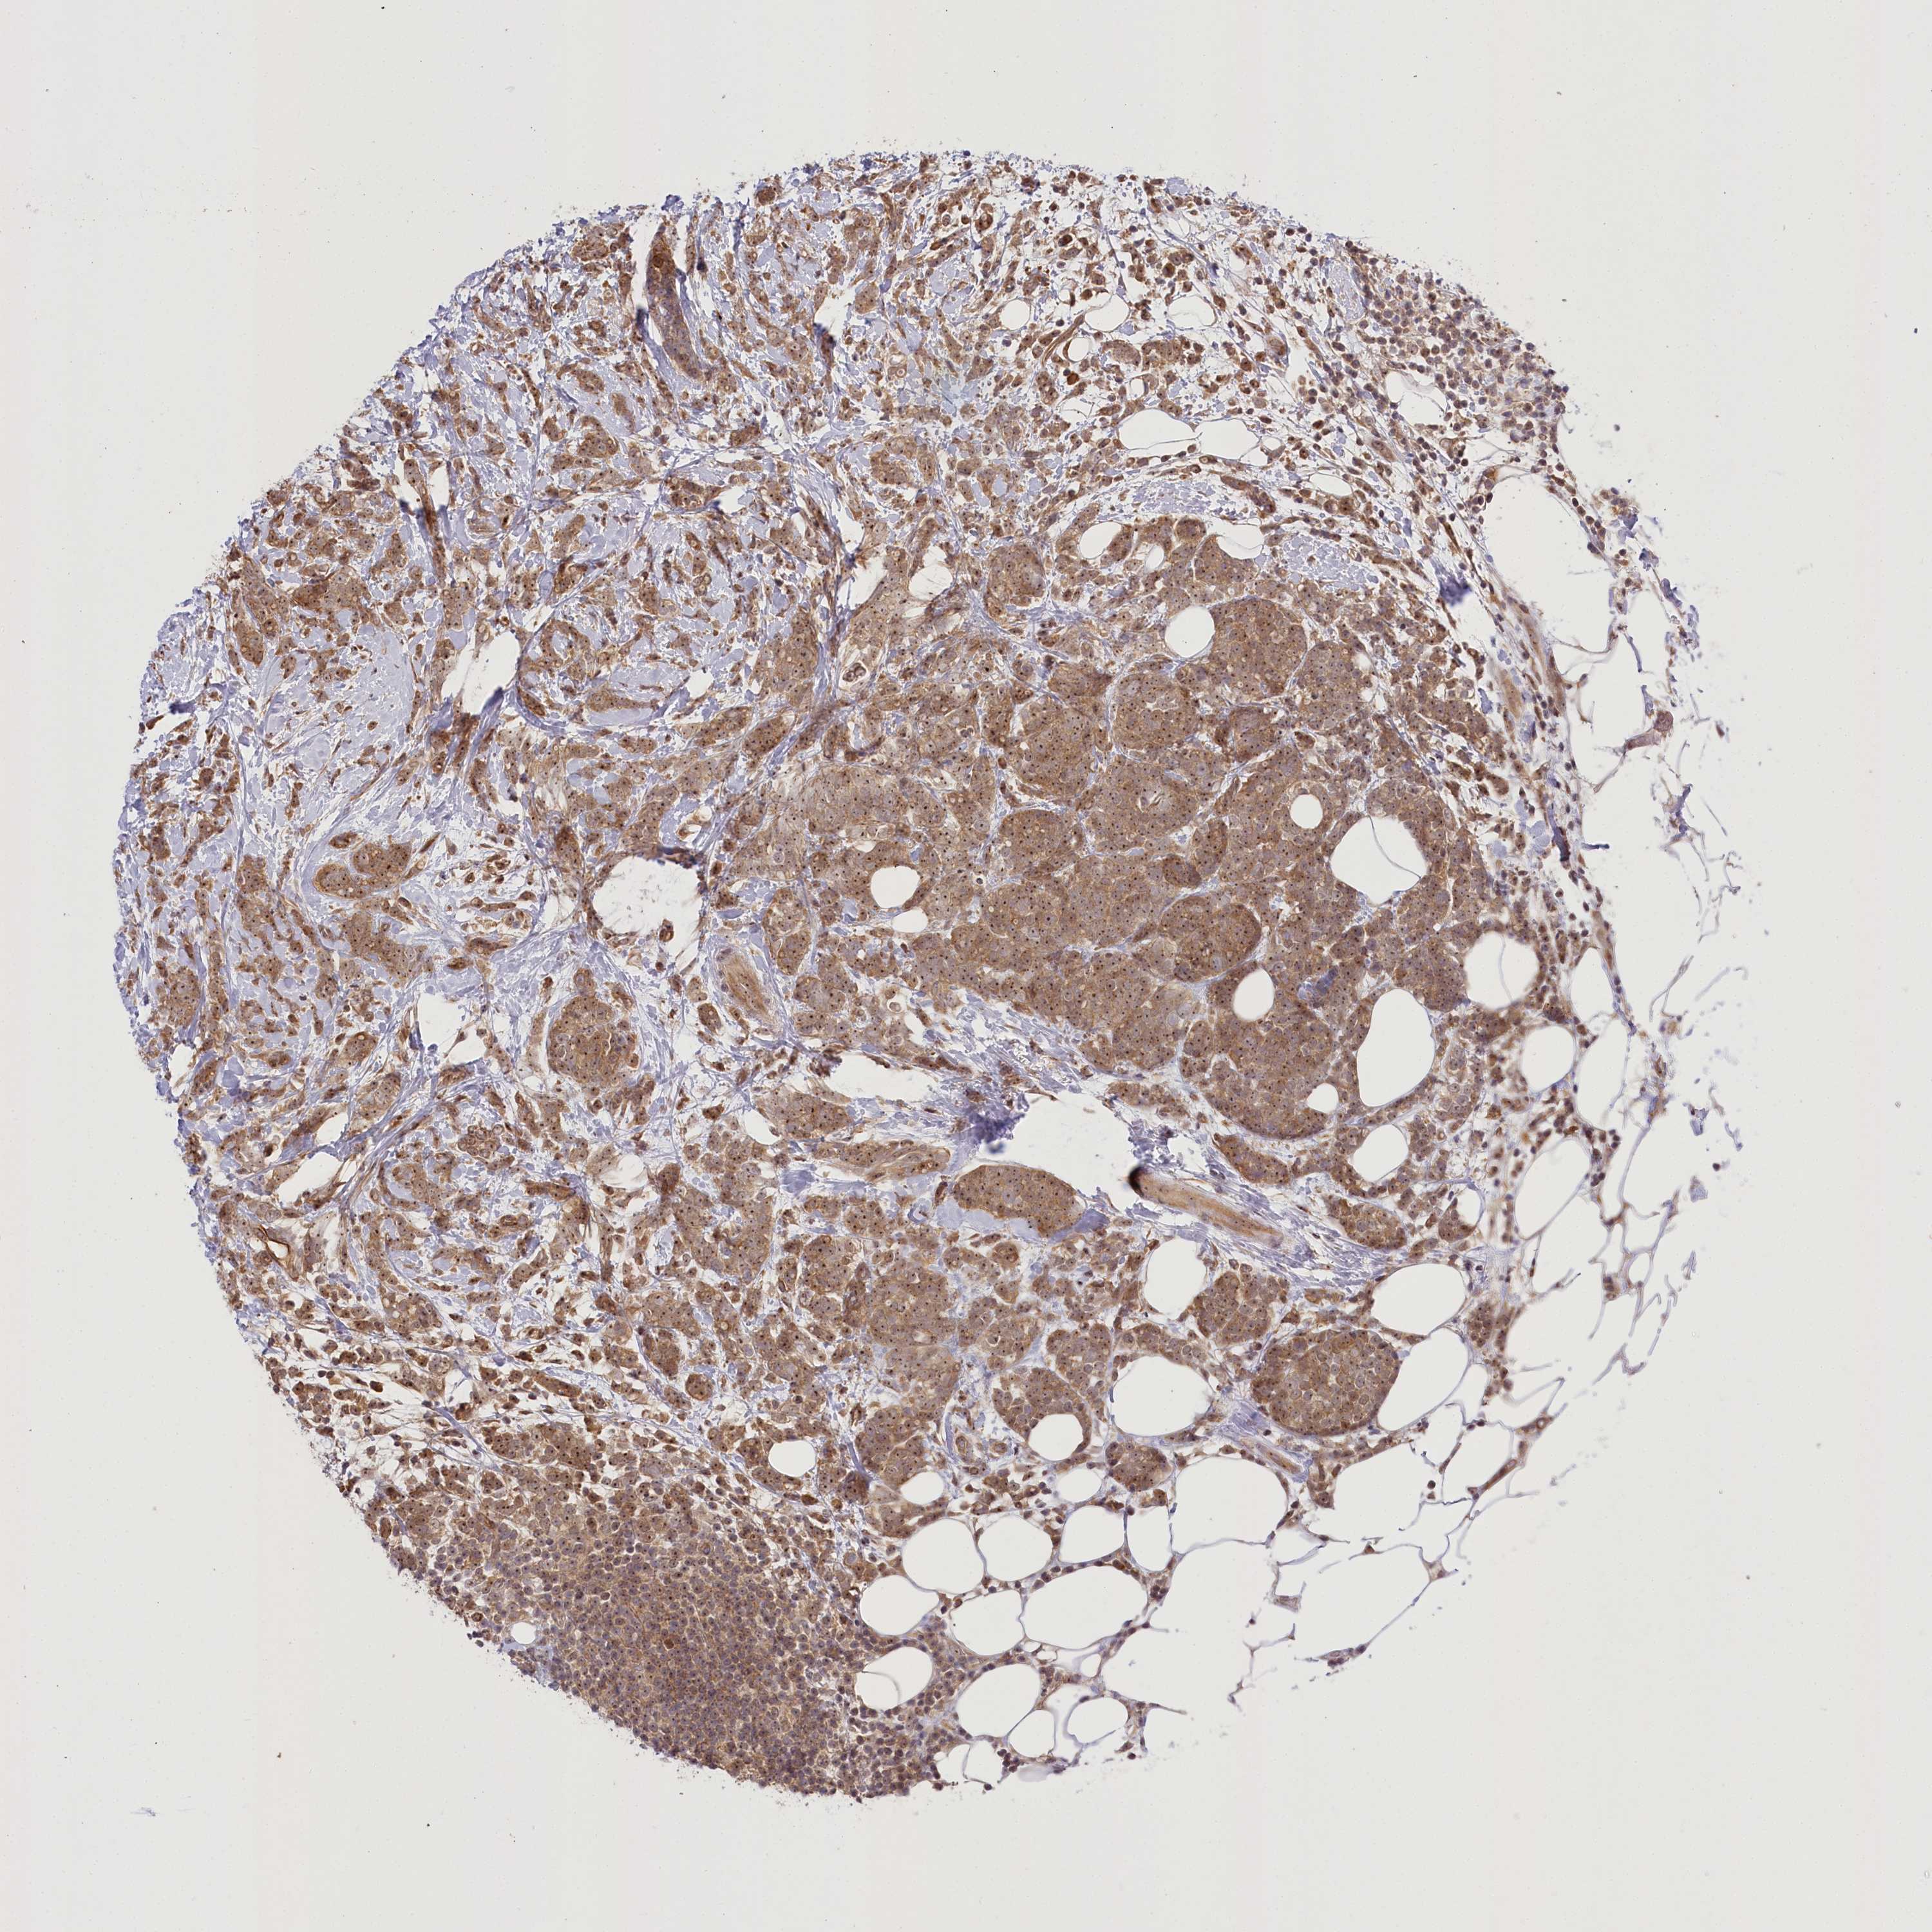

CANCER BREAST CANCER Show tissue menu

BRCA TCGA BRCA VALIDATION PROTEIN EXPRESSION